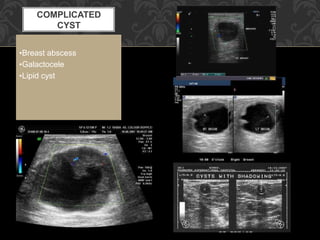

COMPLICATED

CYST

•Breast abscess

•Galactocele

•Lipid cyst